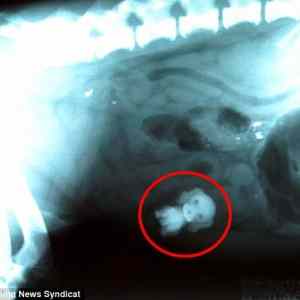

dog-eat-dog.jpg

yo dawg we herd u like dawgs so we put dawg in yo dawg